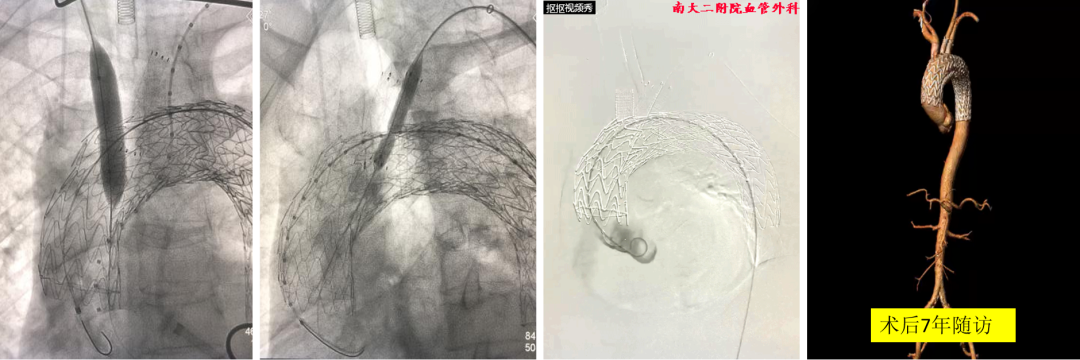

典型病例:一例TEVAR术后三个月发现内漏的患者,采用原位三开窗技术,依次开通左颈总动脉、头臂干、左锁骨下动脉。在有效脑保护下完成操作,术后七年随访效果理想。

另一例逆撕至头臂干的A型夹层患者,在ECMO辅助下行原位三开窗,术中虽出现心跳骤停,但通过ECMO模式转换成功救治,随访六七年CT显示良好。

技术改进:通过3D打印模型辅助术中操作,先对准左颈总动脉,再对准左锁骨下动脉,用球囊扩张固定后再释放支架,为纠错和防止移位争取时间。

复杂病例应用:巨大弓部动脉瘤(5.5cm)且左锁骨下动脉位于瘤腔内:在预开窗基础上加做左锁骨下动脉内嵌分支,配合3D打印模型辅助和束径技术,术后随访效果理想